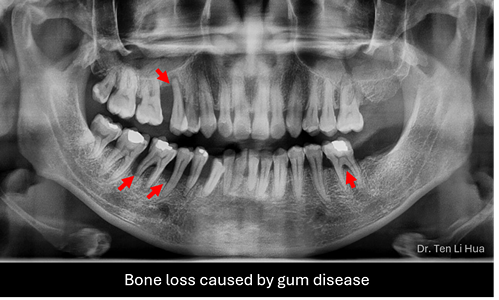

Your journey to healthier gums starts with a thorough examination of your gums and teeth. Dental x-rays will be taken to assess the bone level around your teeth which helps determine the severity of gum disease and any bone loss.